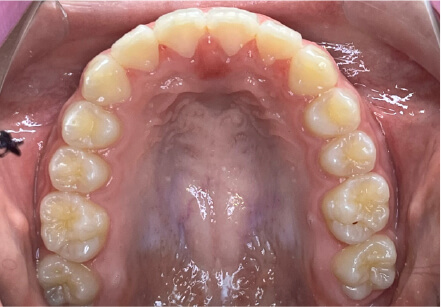

叢生の症例

10歳

/

女性

相談内容

スペース不足

カウンセリング・診断結果

myoからの移行。スペース不足のためインビザライン開始。

治療内容・方法

全額アライナー矯正

術後の経過・現在の様子

クリアライナー使用

治療のリスク

痛み・歯根吸収・歯肉退縮・虫歯・後戻り

費用・治療期間

(インビザのみ)385,000円、1年2ヶ月 + myo3年4ヶ月